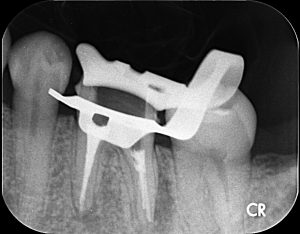

袖ケ浦市の患者さんの歯の根っこは一般的な数よりも多く、その根っこが治療されていなかったために膿が溜まり痛みや腫れを引き起こしていました。レントゲンでは大きく見えますが、歯の根っこは髪の毛1本ほどの細さしかありません。それを肉眼で見つけしっかりと根っこの中の細菌や汚れを綺麗にすることはほぼ不可能です。当院では、20倍以上に拡大できるマイクロスコープ(歯科用顕微鏡)を使用し、根っこの先まで確認しながら根管治療を行っています。

治療器具を歯の根っこに入れて根っこの先まで治療できているか確認したのが上のレントゲンです。しっかりとそれぞれの根っこの先まで器具が到達しているのが確認できます。

治療後(根管充填後)

様々な治療器具や消毒薬を使い根っこの中を徹底的に洗浄をします。その後、根っこの中につめる根管充填材を詰め終わった後のレントゲンです。それぞれの根っこの先までしっかりお薬が入っています。当院では、体と相性がよく殺菌効果の高いバイオセラミックを使用しています(保険診療では使用できません)。バイオセラミックについて詳しくはこちら